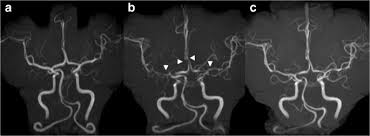

Hidden Moyamoya Disease Mimicking Reversible Cerebral Vasoconstriction Syndrome